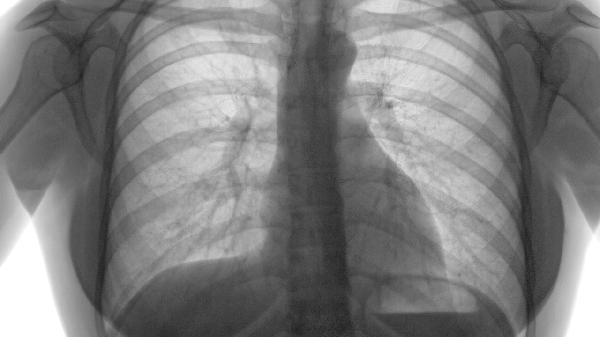

1、肺功能评估:

第一秒用力呼气量占预计值的百分比是判断预后的重要指标。如果这个数值低于35%,说明身体的氧气交换能力明显下降,右心负担加重,可能会加速多个器官功能衰竭。规范使用支气管扩张剂配合长期吸氧有助于延缓肺功能的进一步恶化。